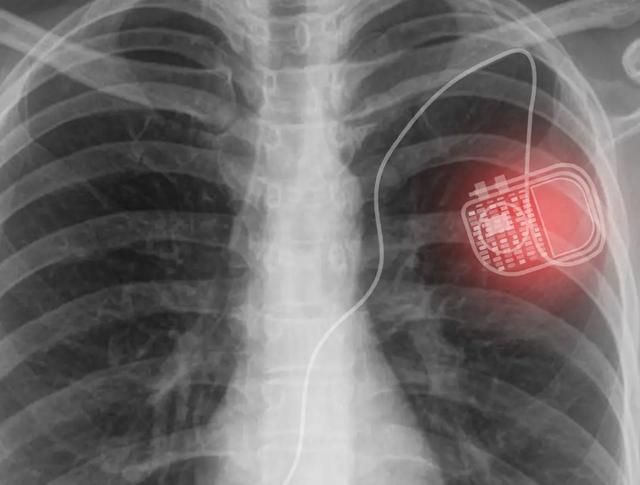

在过去的几十年中,医疗技术在植入装置的范围和效率方面取得了各种进步。例如,医学研究的发展导致了电子植入物的出现,例如用于调节心率的起搏器和控制脊髓液流动的脑脊髓分流器。

这些医疗设备中的大多数,包括起搏器,都需要恒定的能量来运行。自然地,这会带来一些限制:为植入物提供能量的电池寿命有限。一旦电池电量耗尽,别无选择,只能执行侵入性手术来更换电池,这会带来手术并发症的风险,例如瘀伤,感染和其他不良事件。

这个新颖的系统由两部分组成:一个可贴在皮肤上的Micro LED光源贴片-可以产生可穿透组织的光子-以及集成在医疗植入物中的光伏设备-可以捕获光子并产生电能。该系统提供了一种可持续的方式,可以为医疗植入设备提供足够的功率,从而避免任何高风险的更换方法。Lee说:“当前,缺乏可靠的电源限制了植入设备的功能和性能。如果我们能够确保体内足够的电力,那么可以开发出具有多种功能和高性能的新型医疗植入物。”